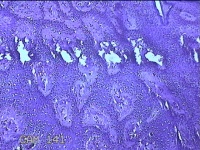

左侧臀部结节

性别

女

年龄

24岁

临床诊断

皮下结节

一般病史

发现左侧臀部结节1年余。

标本名称

大体所见

灰白暗红色带皮肤样结节0.7x0.3x0.2cm一个,表面糜烂,切开结节呈实性,切面灰白暗红色,质软。

图4